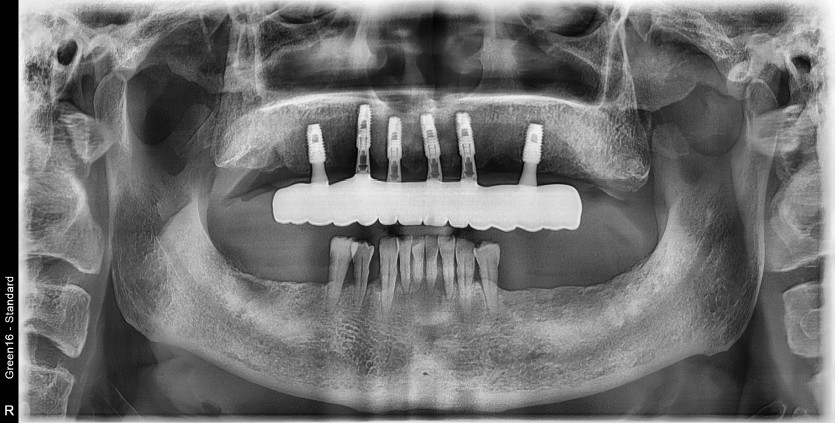

풀아치 증례입니다.

6개의 임플란트로 완성하였습니다.